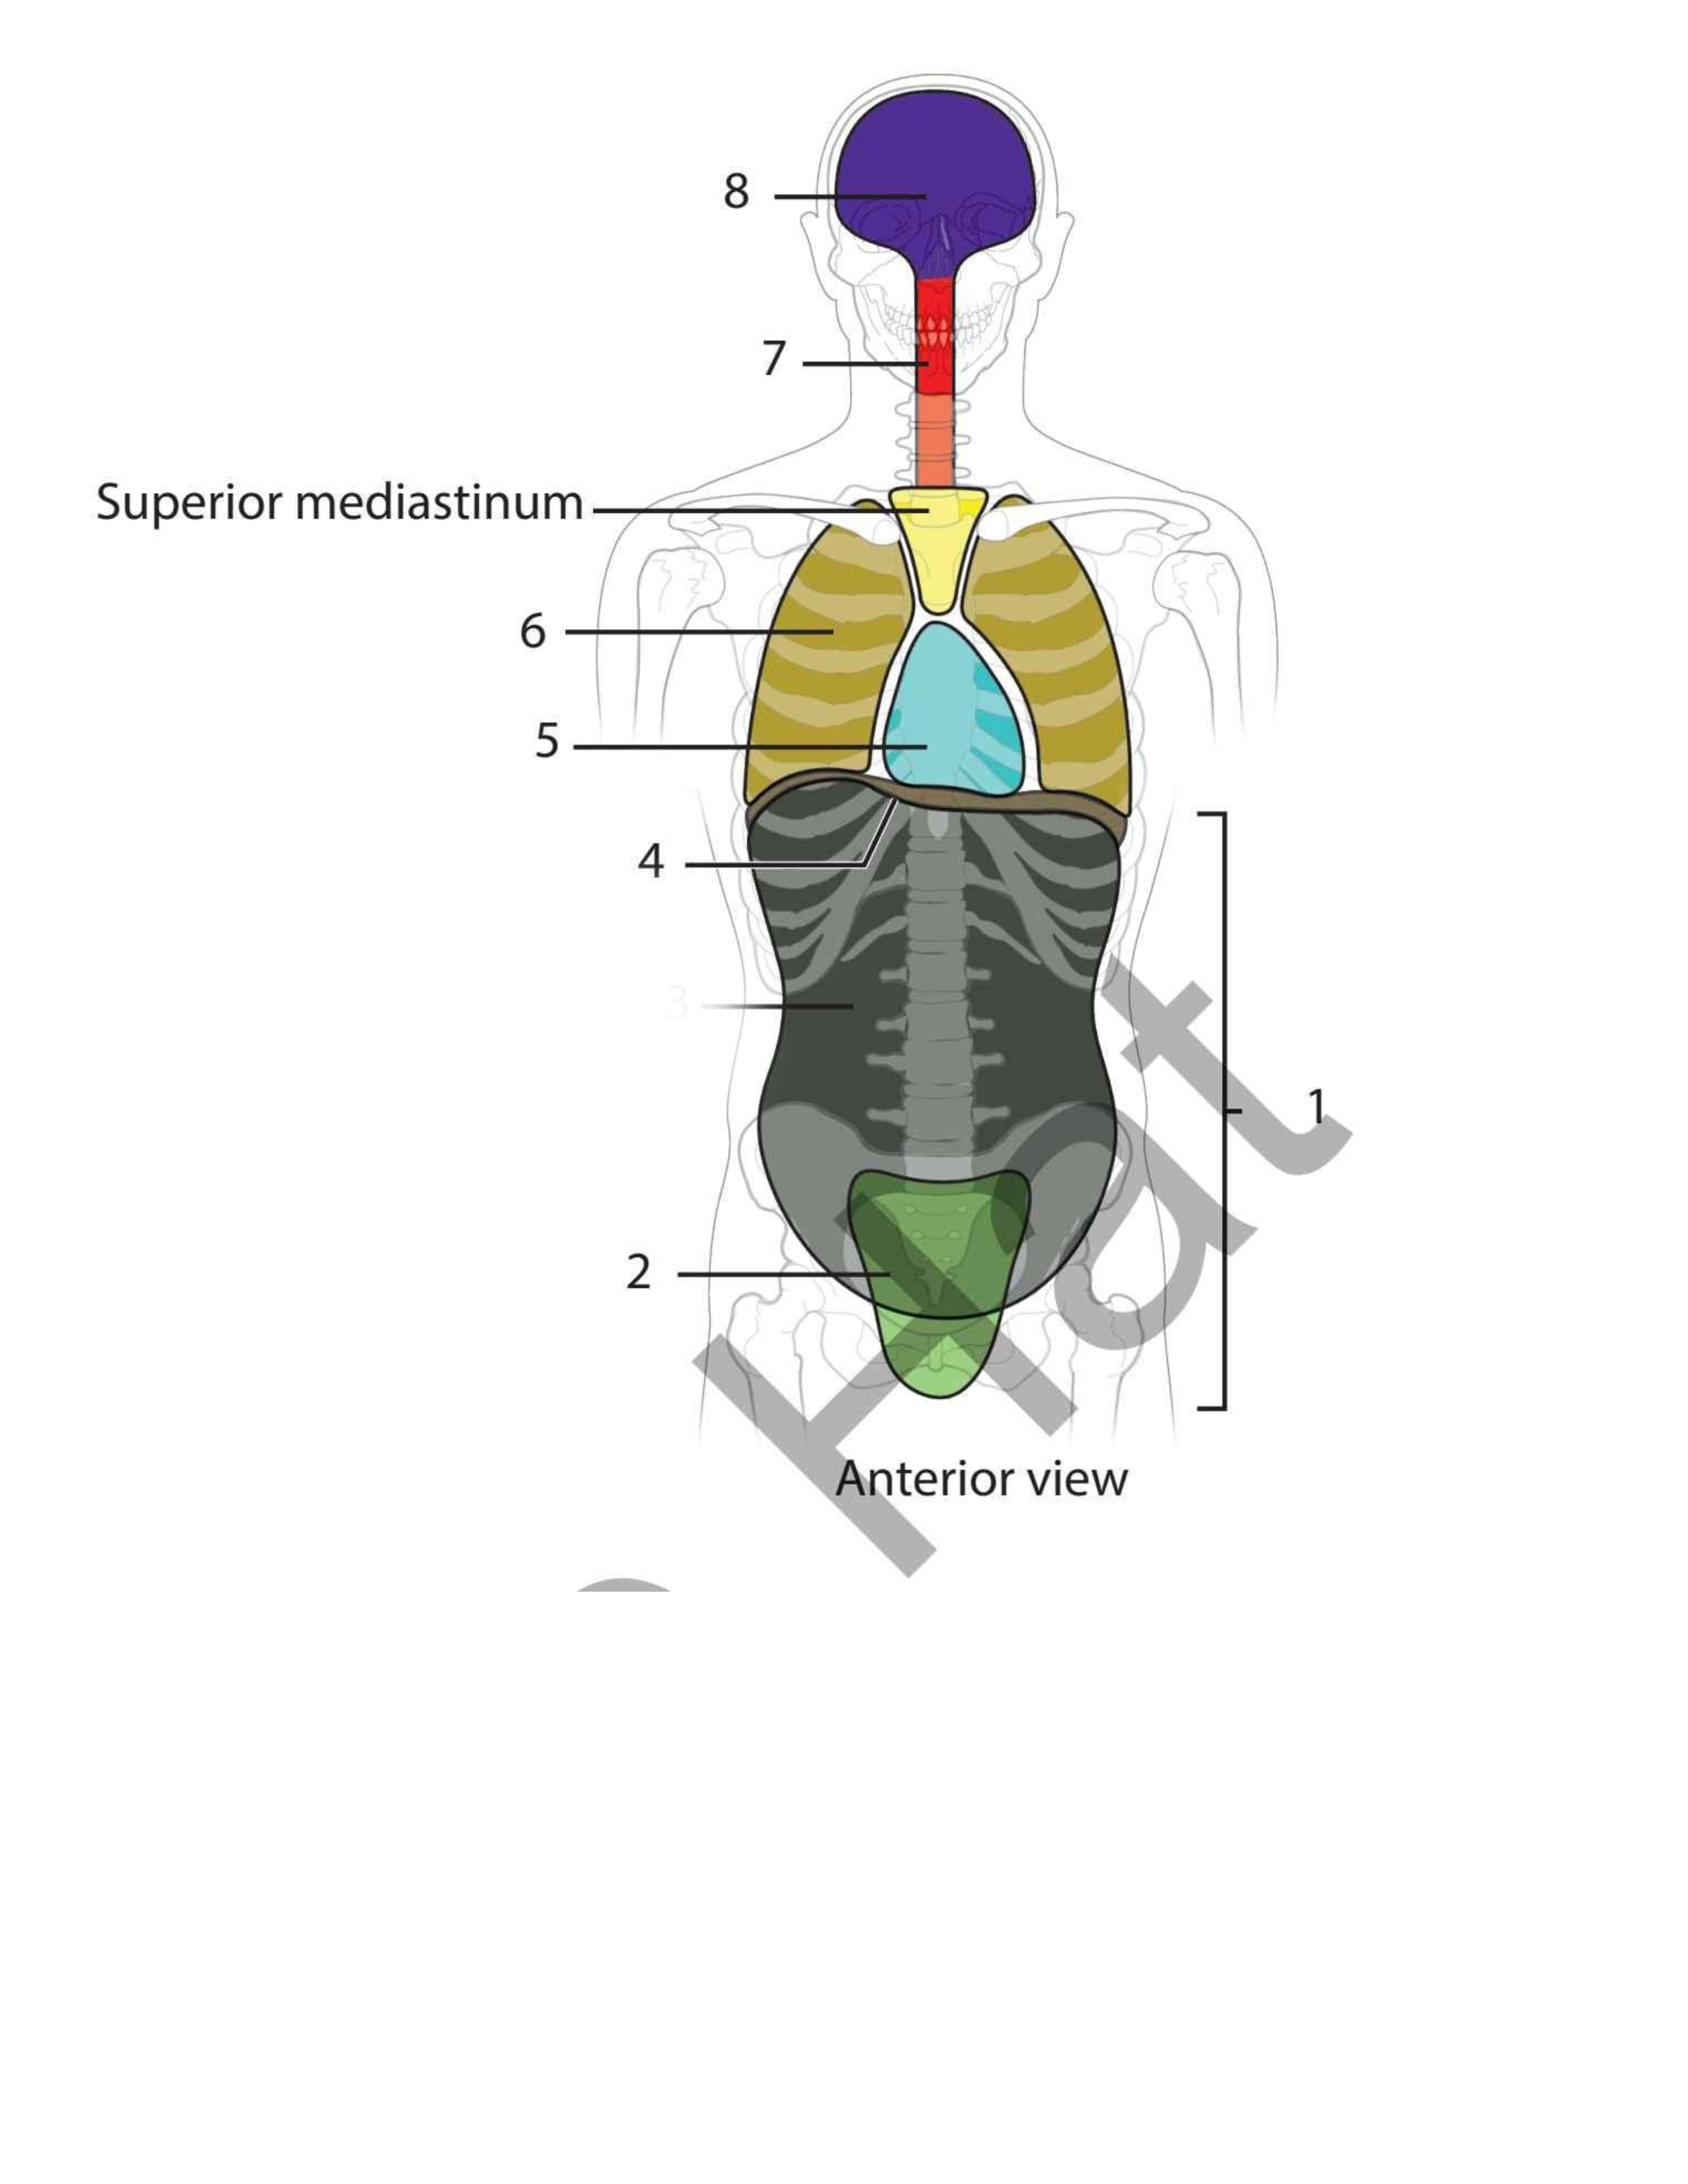

Pelvic

Abdominal

Diaphragm

Pericardial

Pleural

Vertebral

Cranial